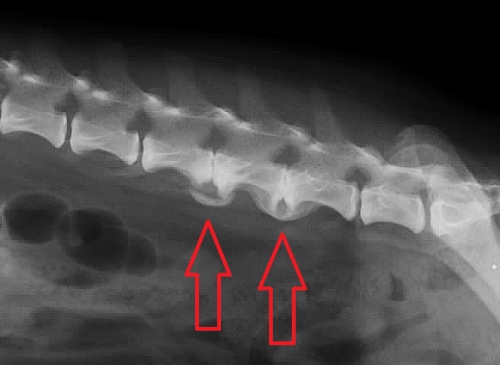

下のレントゲン写真は第4~5腰椎、第5~6腰椎間の変形性脊椎症です。赤矢印の先に隣り合う腰椎の間に形づくられた「椎骨のブリッジ」形成がみられます。こうしたレントゲン像は「無症状にみえる」虫高齢犬でしばしば観察される変化です。